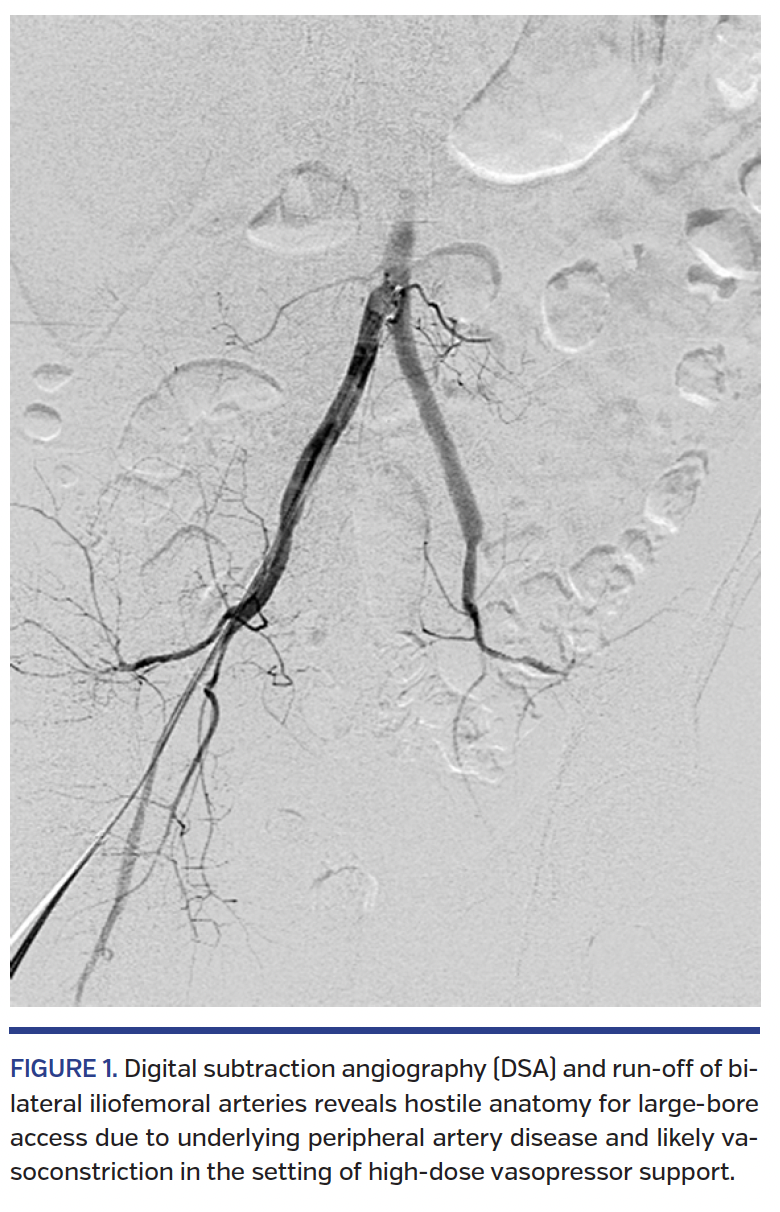

Given the severity of cardiogenic shock, the patient was emergently considered for insertion of an Impella 5.0 device to allow for stabilization and further evaluation of advanced heart failure therapies including transplant and durable LV assist device (LVAD) placement. A heart team discussion with advanced heart failure, interventional cardiology, and cardiothoracic surgery physicians agreed on the choice of support and preference for percutaneous placement. Digital subtraction angiography (DSA) and run-off of bilateral iliofemoral arteries were performed, which revealed hostile anatomy for large-bore access due to underlying peripheral artery disease and likely vasoconstriction in the setting of high-dose vasopressor support (Figure 1; Video 1). Angiography of the right axillary and subclavian arteries demonstrated they were relatively modest in caliber with minimum diameter of 3.8-4.7 mm by quantitative vascular angiography, but free of apparent atherosclerosis, calcification, or tortuosity (Figure 2A, Video 2). The right axillary artery was selected as the approach for percutaneous Impella 5.0 placement.